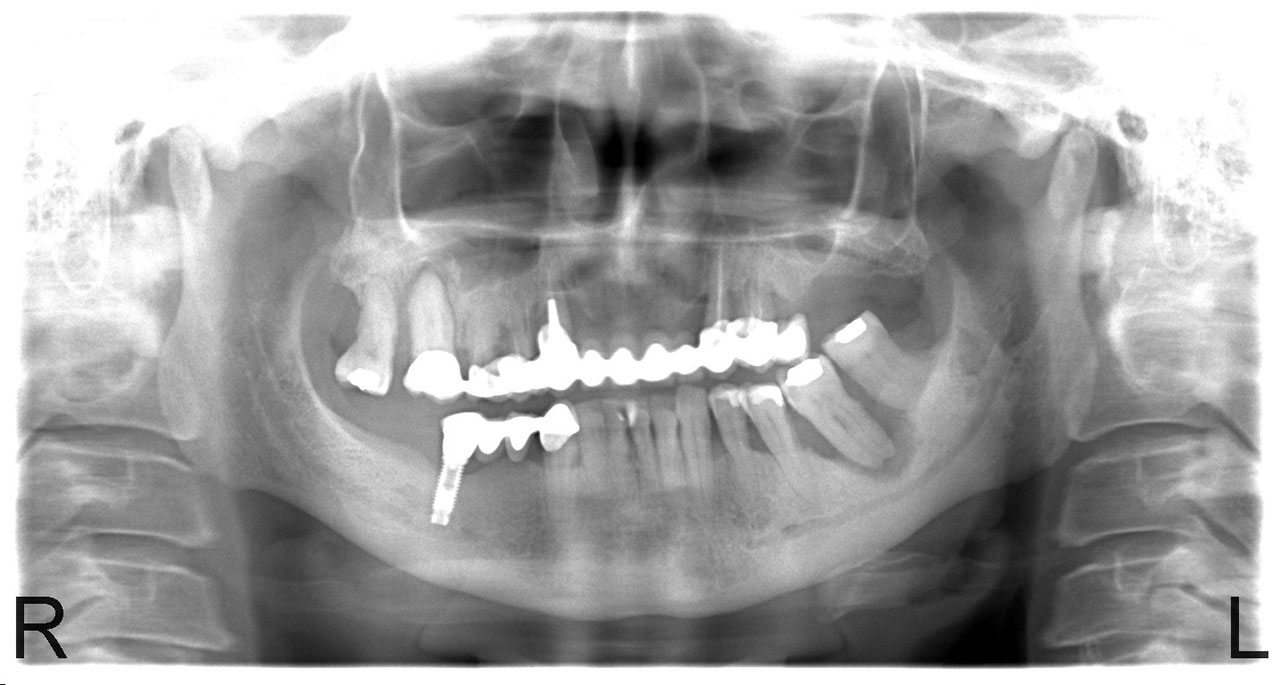

• esettanulmany-04

Impantáció előtt, súlyos fogágy pusztulás, gyulladás látható.

• esettanulmany-06

Impantátumok a végleges híddal.